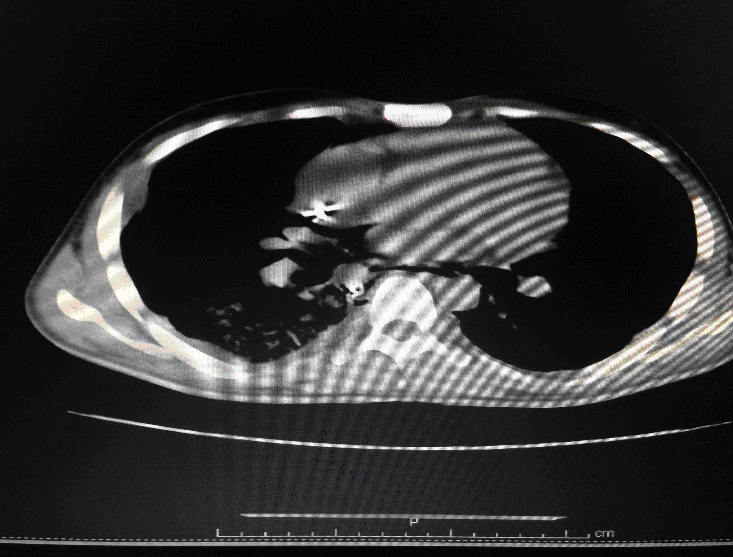

24 year old male, who is a K/C/O Embryonal Ca Testis- S/P Orchidectomy done 6 months back followed by chemotherapy with Bleomycin for 4 cycles, had presented with complains of cough since 1month and fever since 2 weeks. Associated breathing difficulty was also present and cough was productive. On arrival in the ED he was conscious ,oriented and talking .His vitals showed a HR of 125/min, BP of 90/60 and Saturation was 80%in Room Air. His RR was 35/min and was febrile. Work of breathing was greatly increased and bilateral coarse crepitations were present. Blood gases revealed Respiratory Acidosis. A trial of Non Invasive Ventillation (Bi PAP) was tried initially but failed. He was intubated immediately and put on pressure controlled ventilation.IV fluids were started and early antibiotics initiated. Initial CT Thorax showed features suggestive of Brochiolitis Obliterans organizing Pneumonia (BOOP).

Following admission in the Medical ICU, Bronchoscopy was done and started on IV steroids and higher End Antibiotics. His bronchial wash grew ESBL Klebsiella and Pseudomonas. His other organ functions were not deranged. Repeat CT Thorax was taken which showed ground glass opacities, septal thickening, traction bronchiectasis, pleural thickening which was all S/o Drug induced Toxicity-Bleomycin.

High-resolution computed tomography (HRCT) of the chest is more sensitive than chest radiography in identifying lung abnormalities in bleomycin-exposed patients. HRCT patterns usually reflect the underlying histopathology . Diffuse alveolar damage is associated with airspace consolidation and ground-glass opacities. Findings suggestive of end-stage fibrosis include extensive reticular markings, traction bronchiectasis, and honeycombing. Organizing pneumonia manifests as ground-glass opacities in a bilateral but asymmetric pattern or by airspace consolidation with a subpleural or peribronchial distribution. Organizing pneumonia may occasionally present as one or more nodular densities that may mimic tumor metastases.